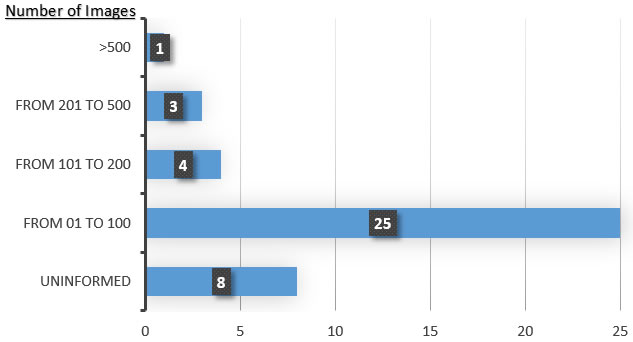

Sixty-one percent (61%) of the relevant papers used data sets containing between 1 and 100 X-ray images ((Lin et al.,, 2012), (Li et al.,, 2007), (Son and Tuan,, 2016), (Alsmadi,, 2015), (Lin et al.,, 2015), (Lin et al.,, 2010), (Cameriere et al.,, 2015), (Jain and Chen,, 2004), (Dighe and Revati,, 2012), (Lin et al.,, 2014), (Bruellmann et al.,, 2016), (Economopoulos et al.,, 2008), (Gráfová et al.,, 2013), (Kaur and Kaur,, 2016), (An et al.,, 2012), (Ehsani Rad et al.,, 2013), (Tikhe et al.,, 2016), (Lin et al.,, 2013), (Ajaz and Kathirvelu,, 2013), (Mohamed Razali et al.,, 2014), (Indraswari et al.,, 2015), (Modi and Desai,, 2011), (Amer and Aqel,, 2015), (Li et al.,, 2012), (Senthilkumaran, 2012a, )). Eight of the reviewed articles did not present information about the data set used ((Li et al.,, 2006), (Senthilkumaran, 2012b, ), (Trivedi et al.,, 2015), (Niroshika et al.,, 2013), (Ali et al.,, 2015), (Razali et al.,, 2015), (Keshtkar and Gueaieb,, 2007), (Geraets et al.,, 2007)). Four of the papers reviewed used between 101 and 200 images ((Wang et al.,, 2016), (Nomir and Abdel-Mottaleb, 2008b, ), (Lurie et al.,, 2012), (Nomir and Abdel-Mottaleb, 2008a, )). Three used between 201 and 500 images ((Huang and Hsu,, 2008), (Abaza et al.,, 2009), (Hasan et al.,, 2016)). Only one among the papers reviewed used more than 500 images in their experiments (Said et al.,, 2006). In general, the reviewed articles exploited data sets containing X-ray images with small variations (i.e., varying only with respect to the number of teeth). In addition, as shown in the previous section, there is a predominance of intra-oral radiographs (which show only a part of the teeth) rather than extra-oral radiographs (which present the entire dental structure in a single image). Figure 1 depicts the number of works versus number of images used in each group of work.